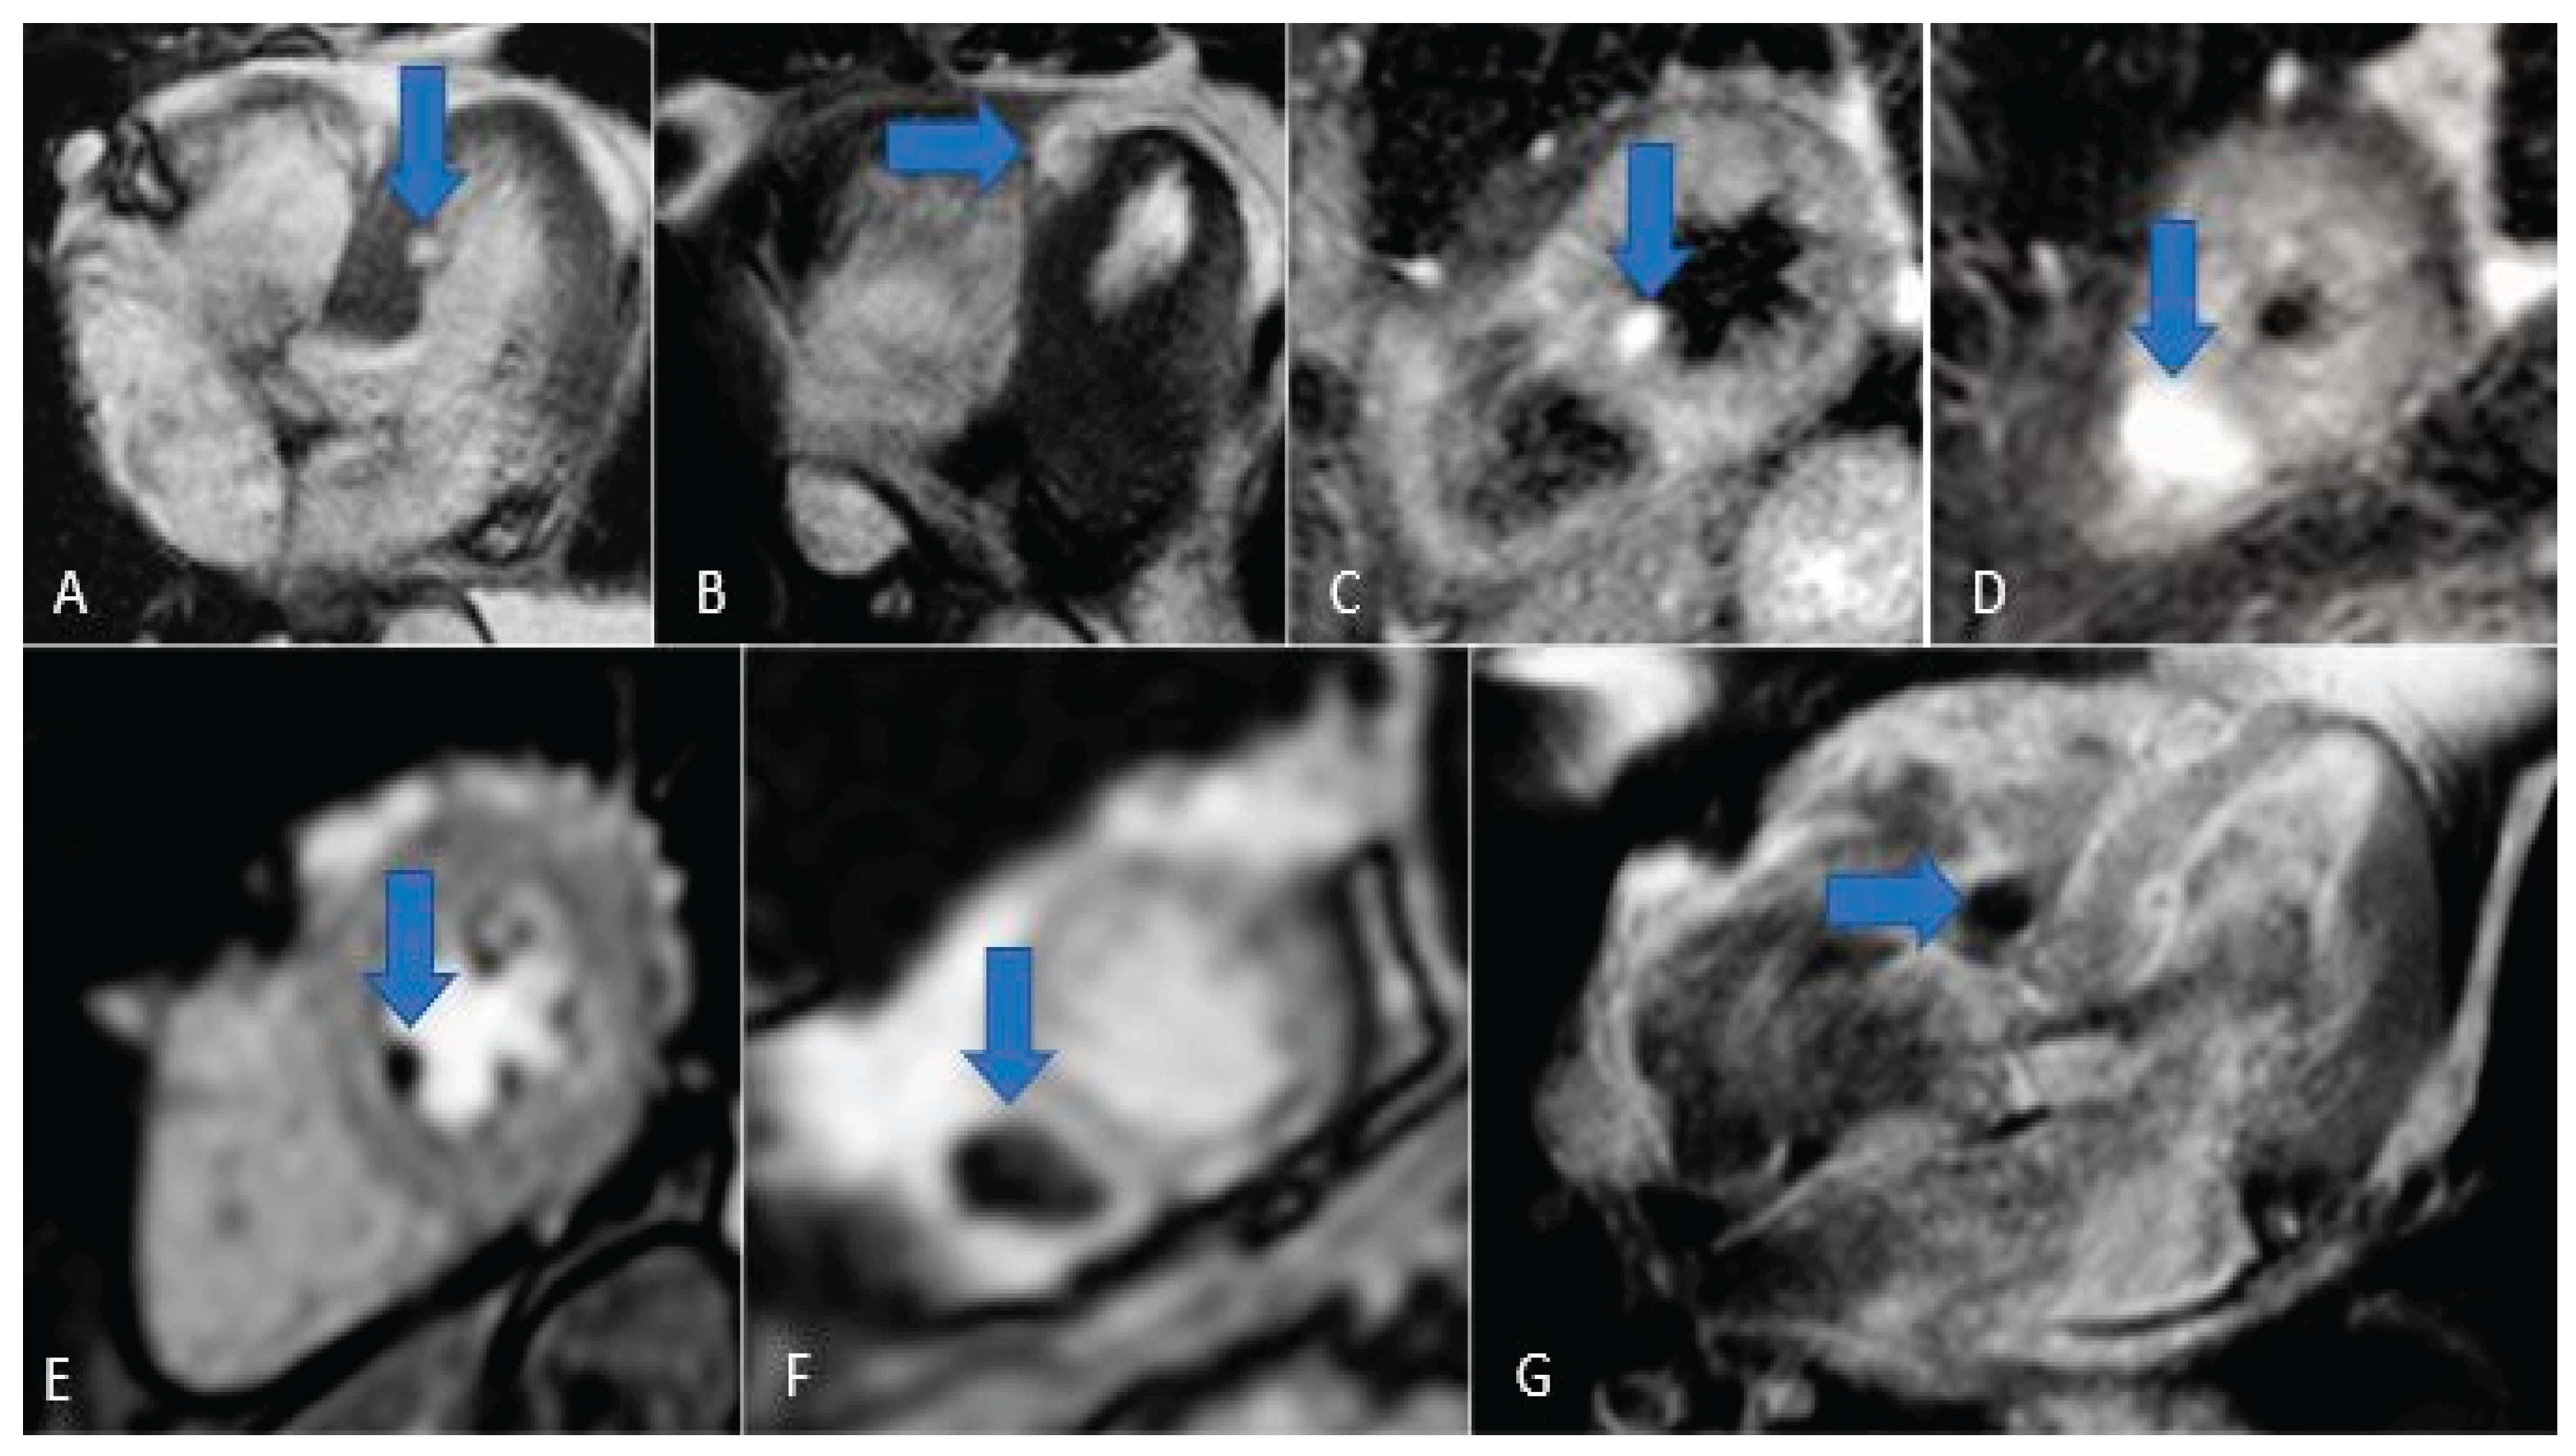

Figure 15. Chordoma metastasis. Note the hyperintensity in T2/STIR sequences (A, B, C and D) and the hypointensity in perfusion and LGE sequences (E, F and G).

Cardiac metastases are secondary tumors involving the heart, representing the spread of tumors via the lymphatic and blood vessels. Although rare, cardiac metastases are much more common than primary cardiac tumors, with a ratio of about 30:1 and a frequency of 18% in oncological patients. The most common primary tumors that metastasize to the heart include lung cancer, breast cancer, renal cancer, ovarian cancer, pleural mesothelioma, malignant melanoma (Figure 13ta), chordoma (Figure 14) and lymphoma [52,53].

MRI usually shows hypointense images in T1 and hyperintense in T2, with avid contrast enhancement after administration. Malignant melanoma shows T1 hyperintensity due to the paramagnetic properties of melanin, low intensity in , T2 images and heterogeneous appearance on LGE imaging [54]. These characteristics allow for a specific diagnosis without the need for a biopsy [3].